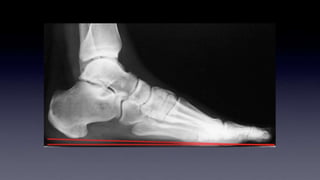

What is pathologic

Flat

Normal

High